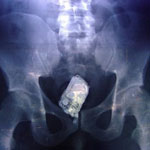

Jelenleg ugyanis az a helyzet, hogy a börtönökben ülő bűnözők számára mindent megér, hogy bejuttassák a mobilt a zárkába. Míg régen a ráspolyt sütötte a gondos mama a kenyérbe, ma a mobilokat. De van, hogy műlábban, gyümölcsben vagy borotvahabban juttattják be a maroktelefont. A legkellemetlenebb persze (legalábbis a rabokra nézve) mikor maguk az elítéltek viszik be különböző testnyílásukba helyezve az apró készülékeket. Ebből is kitűnik, mi mindent megtesznek a dutyilakók szeretteik felhívásáért.